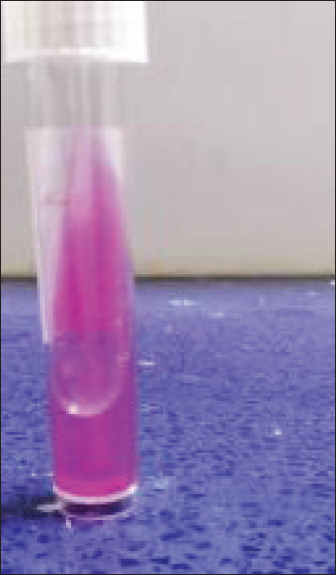

The current study demonstrated that Raoultella planticola exhibits mild pathogenicity when administered via the intranasal route in rabbits. The observed clinical signs (dullness, nasal and ocular discharge) and pathological findings (pulmonary emphysema) suggest that this bacterium can induce respiratory infection under experimental conditions. These et al findings align with Podschun (1998), who reported that Raoultella planticola is an environmental bacterium commonly found in water, soil, and plants, capable of colonizing humans and animals. The bacterium is a facultative anaerobic Gram-negative bacillus belonging to the Enterobacteriaceae family. It forms mucoid colonies on MacConkey agar due to polysaccharide capsule production (Figs. 1 and 2), making it morphologically and biochemically similar to Klebsiella spp. (Table 1).

Fig. 1. Urease test.